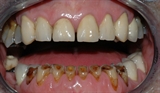

figur III

Bildet viser et eksempel på alvorlig tanngnissing.

Man kan se hvordan tennene er svært slitt.